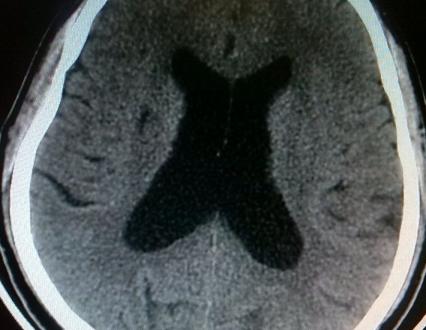

脑梗塞后遗症这是常见的脑血管病,它多发于老年人,复发率非常高。恢复期治疗目的就是改善头晕头痛、肢体麻木障碍、语言不利等症状的,使之达到最佳的一个状态;同时降低脑梗塞后遗症的高复发率。接下来就为大家详细的介绍一下。

脑梗塞后遗症属于高复发不可逆性的慢性脑血管意外,病人出院后仍需按医生嘱咐规律服药,控制好高血压、高血脂、糖尿病等动脉硬化的基础病变,并定期到医院复查。常用治疗脑梗塞后遗症的有效药物包括抗血小板聚集类药物,如拜阿司匹林;脑保护营养药物,益气活血开窍止痛药物。